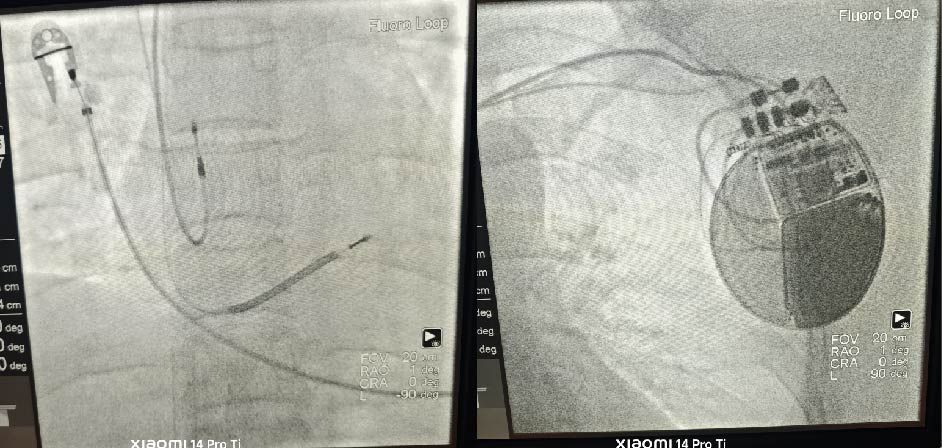

近日,我院心血管内科团队成功为一名恶性心律失常、心跳骤停患者在ECMO辅助下植入超长续航双腔植入式心律转复除颤器(ICD),系我院首例,创下我院危重症心脏介入治疗新纪录。

该患者为41岁中年女性,因心室颤动伴意识丧失入院,急诊科在裴红红主任统筹下,潘龙飞副主任医师心肺复苏成功后行有创通气并植入VA-ECMO进行循环支持。ECMO辅助下,患者仍反复发作心室颤动,具有ICD植入指征,但常规ICD植入术风险极高,术中随时可能发生伤口止血困难、血流动力学不稳定、心跳骤停。心血管内科邓捷主任、张岩副主任领衔的多学科团队经充分评估,考虑到患者预期寿命长、除颤需求预期较低、手术风险较高,超长续航ICD更具优势,决定启动“ECMO护航+超长续航双腔ICD植入”创新方案。

经过周密的术前准备,在邓捷主任的指导下,手术由张岩副主任主刀,张春艳副教授、韩拓医生担任助手,心血管内科护理团队辅助,ECMO护航下仅用2小时顺利完成超长续航双腔ICD植入,程控提示ICD功能良好。术后患者顺利撤离ECMO支持,手术伤口愈合良好,ICD工作正常,已出院回归正常生活。此次植入的超长续航ICD设备预计使用寿命达15年以上,相较于普通ICD,减少了后续因电池耗竭而需要进行的更换手术次数,大大降低长期医疗成本并显著提升患者的生活质量。